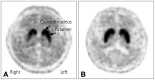

Parkinsonism is a clinical syndrome presenting with bradykinesia, tremor, rigidity, and postural instability. Nonmotor symptoms have recently been included in the parkinsonian syndrome, which was traditionally associated with motor symptoms only. Various pathologically distinct and unrelated diseases have the same clinical manifestations as parkinsonism or parkinsonian syndrome. The etiologies of parkinsonism are classified as neurodegenerative diseases related to the accumulation of toxic protein molecules or diseases that are not neurodegenerative. The former class includes Parkinson's disease (PD), multiple-system atrophy, progressive supranuclear palsy, and corticobasal degeneration. Over the past decade, clinical diagnostic criteria have been validated and updated to improve the accuracy of diagnosing these diseases. The latter class of disorders unrelated to neurodegenerative diseases are classified as secondary parkinsonism, and include drug-induced parkinsonism (DIP), vascular parkinsonism, and idiopathic normal-pressure hydrocephalus (iNPH). DIP and iNPH are regarded as reversible and treatable forms of parkinsonism. However, studies have suggested that the absence of protein accumulation in the nervous system as well as managing the underlying causes do not guarantee recovery. Here we review the differential diagnosis of PD and parkinsonism, mainly focusing on the clinical aspects. In addition, we describe recent updates to the clinical criteria of various disorders sharing clinical symptoms with parkinsonism.